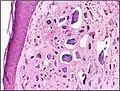

| Micrograph of calcinosis cutis. The calcification is purple (bottom of image). H&E stain. | |

Histopathology of calcinosis cutis in human tissue